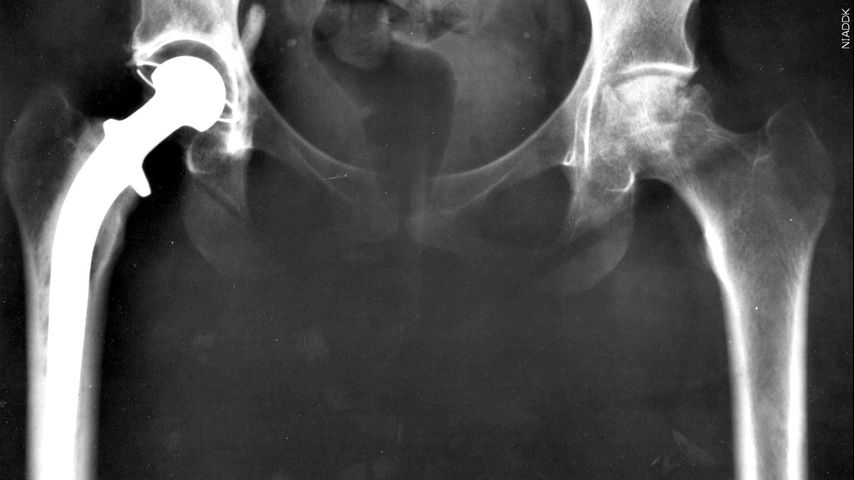

BATON ROUGE — Hip issues are often thought of as something older people deal with. But they can be present at birth.

Hip dysplasia is a condition where the ball and socket of the joint don't fit together quite right. This can lead to joint instability, bone and cartilage damage, early arthritis, and a lot of pain.

"There was always that tradition for pediatric hip surgery for young children. And there's always the field of hip replacement surgery for elder patients. And with hip preservation, we're kind of bridging that gap,” Mayo Clinic orthopedic surgeon Emmanouil Grigoriou said.

Grigoriou says the goal of hip preservation is “to allow patients to retain their own hip joint, their own cartilage, without any limitations or restrictions after surgery, enjoy years and years with their own native hip and potentially even eliminate the need for any future hip replacement surgery."

Hip preservation surgery isn't for everyone, and outcomes are better when problems are diagnosed early and when less arthritis is present.